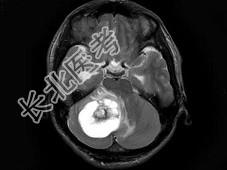

单项选择题男,33岁, 阵发性头痛伴呕吐行走不稳1个月,MRI平扫及增强扫描如图, 最可能的诊断是 ( )

A、右小脑星形细胞瘤

B、右小脑脓肿

C、右小脑血管母细胞瘤

D、转移瘤